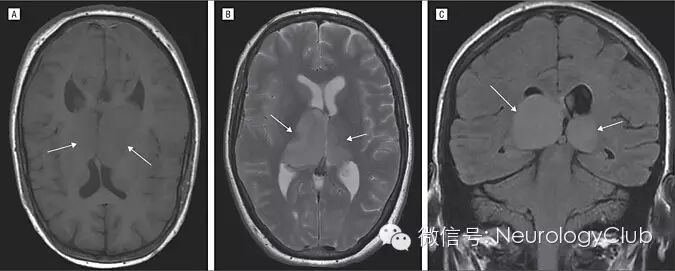

56岁女性,因强直-阵挛发作入院。既往史无殊。查体未见明显异常。白细胞计数12200/μL,中性粒细胞计数10200/μL。头颅MRI提示双侧丘脑不对称肿胀增大,信号均匀,侧脑室受压变形。丘脑病变T1WI等信号,T2WI/FLAIR高信号,注射对比剂后无明显强化。磁共振波谱分析(MRS)提示病变区肌醇,Cr峰出现伴Cr/Cho比值升高,NAA降低。上述影像学提示双侧丘脑胶质瘤。

(A:T1WI;B:T2WI;C:FLAIR)

双侧丘脑胶质瘤常引起行为学改变或痴呆,不伴有感觉或运动异常。本例患者不同于其他案例,而以强直-阵挛发作为主要表现且不伴有脑积水。CT上,双侧丘脑胶质瘤呈边界清楚,等密度的对称或不对称的丘脑肿胀;MRI上,病灶信号均匀,T1WI等信号,T2WI/FLAIR高信号。